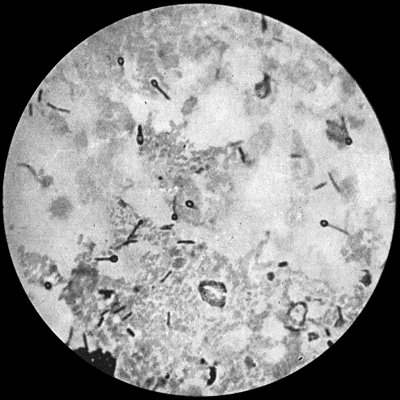

Fig. 3.—Streptococci in Pus from an acute abscess in subcutaneous tissue. × 1000 diam. Gram's stain.

Division takes place in one axis, so that chains of varying length are formed (Fig. 3). It is less easily cultivated by artificial media than the staphylococcus; it forms a whitish growth.